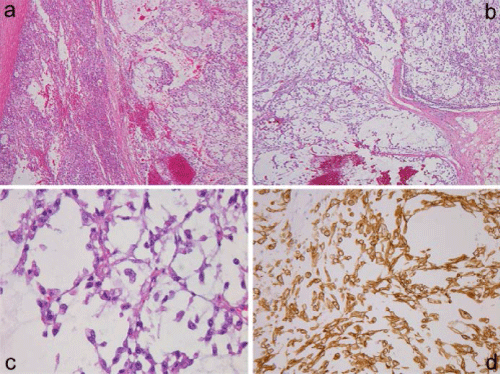

| Figure 2: Surgically removed right adrenal metastasis (a) showing transition between left-sided adenocarcinomatous components and right-sided markedly myxoid area. Low-power view of postmortem lymph node metastasis (b) composed of lobulated myxoid areas containing reticular cancerous proliferation, and the high-power view (c) showing polygonal or spindle cells arranged in short anastomosing cords with an abundant myxoid material, mimicking extraskeletal myxoid chondrosarcoma. Sarcomatous spindle cells in the liver metastasis showing cytokeratin 7 expression (d). |